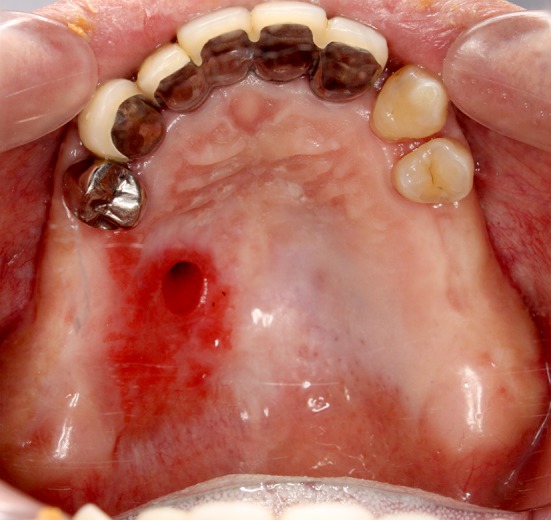

Fig. 1.

Image obtained before the closure of the palatal fistula in case 1. The fistula exists near the palatal median

Fig. 7.

Image obtained before closure of the palatal fistula in case 2. The fistula occurred after the first molar tooth extraction